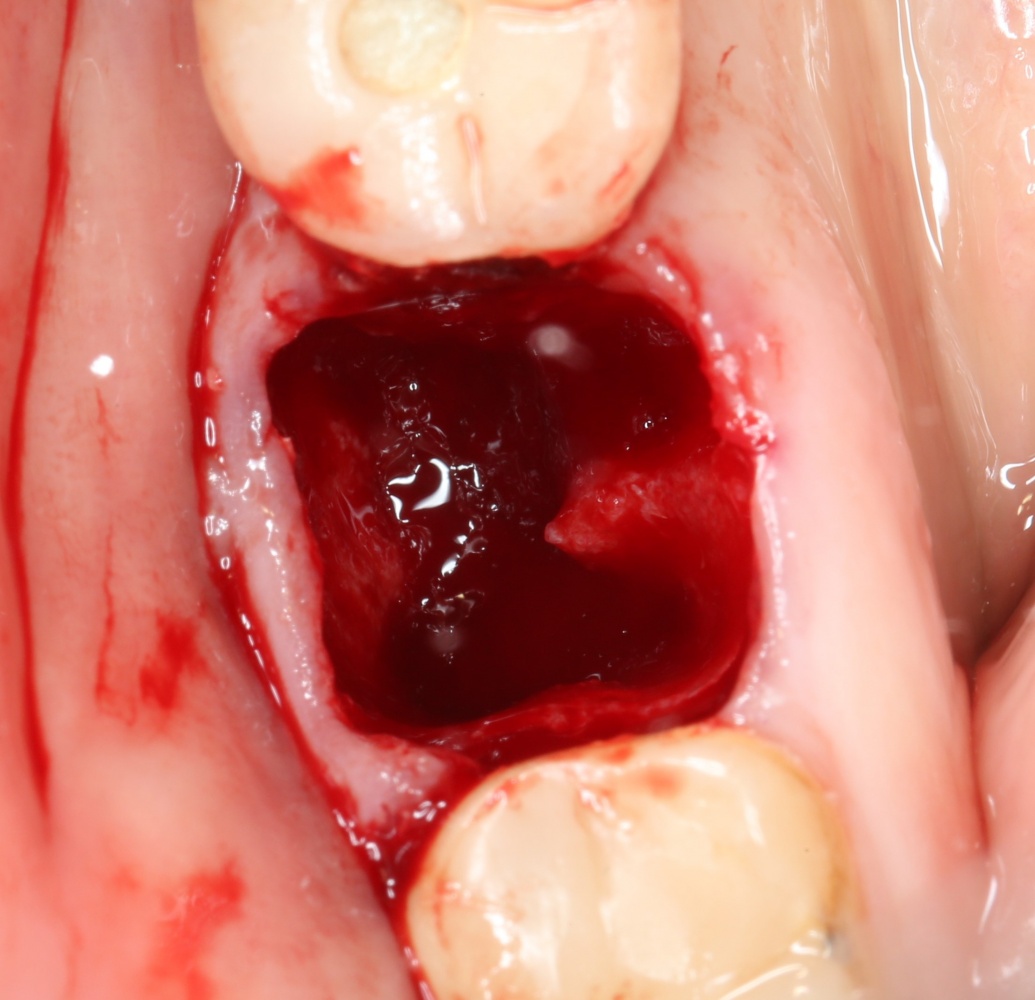

Рекомендации по установке имплантов. Для всех. Часть II.